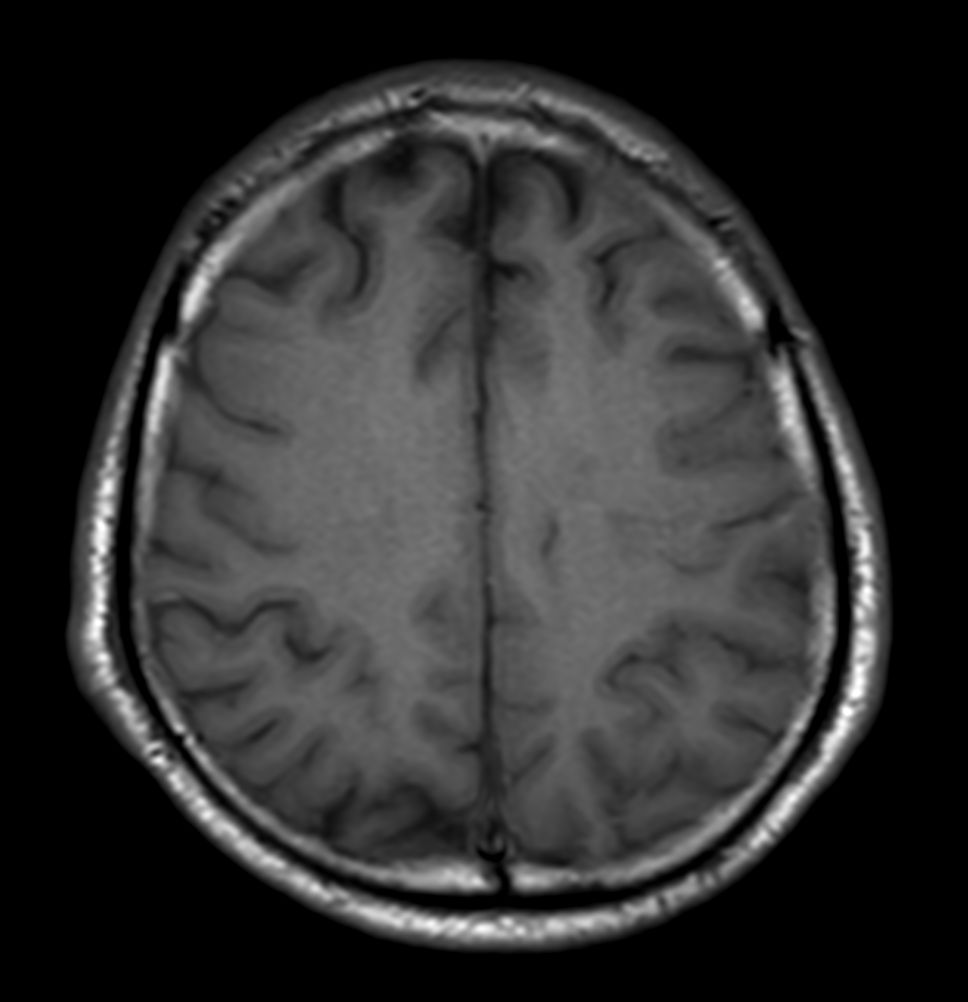

Brain small infarction

Patient with a small brain infarction. Compressed SENSE acceleration is used to speed up sequences while maintaining equal image quality. Three different diffusion methods are included; A fast 52 secs DWI EPI sequence, a high resolution DWI EPI sequence and a TSE based DWI sequence. A SWIp sequence is included offering high resolution 3D susceptibility weighted imaging to enhance contrast for deoxygenated (venous) blood or calcium deposits. 3D APT sequence is included providing contrast-free brain imaging, addressing the need for more confident diagnosis in brain neuro oncology by using the presence of endogenous cellular proteins to produce an MR signal. And a large FOV TOF MR Angiography sequence is included to check on brain vascular anatomy.

Axial T1w SE